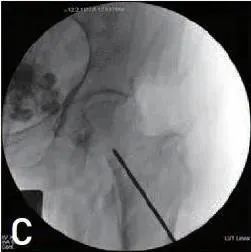

将克氏针固定在近端骨折块上,从内侧和上方操纵克氏针,将近端碎片抬高到远端碎片之外(图1C、D)。

图1 C,D 通过推进和操作克氏针实现髓外复位。